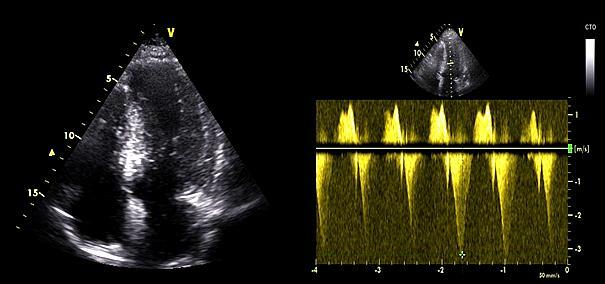

To ensure accurate patient selection, MVOHCM diagnosis was confirmed based on 3 key criteria: (1) a maximum left ventricular (LV) wall thickness of greater than or equal to 15 mm in the absence of any other identifiable cause of hypertrophy, (2) a midventricular pressure gradient of greater than or equal to 30 mm Hg, and (3) a midventricular hourglass-like obliteration due to systolic muscular apposition of the hypertrophic septum against the LV free wall. In some cases, Doppler echocardiography demonstrated a characteristic "signal void" pattern, indicative of abrupt flow cessation across the obliterated ventricle, followed by paradoxical early diastolic flow reflecting the release of previously trapped volume.12 A comprehensive echocardiographic evaluation (Figure 1) was performed to confirm the presence of MVO, characterized by significant myocardial thickening and elevated pressure gradients. This assessment was crucial in identifying candidates suitable for the ablation procedure and optimizing the treatment strategy. Patients were excluded if they had subaortic obstructive HCM, apical HCM, other cardiovascular conditions requiring urgent surgical intervention, or anatomical constraints precluding percutaneous septal reduction therapy.

The procedure was performed under conscious sedation and local anesthesia. As mentioned in our previous study,11 femoral artery access was achieved using two 6-French sheaths—one for the guiding catheter to deliver the ablative agent and another for continuous monitoring of the midventricular gradient throughout the procedure. Femoral venous access was also obtained to place a temporary pacemaker in the right ventricular apex, ensuring readiness to manage potential advanced atrioventricular (AV) blocks during the procedure. A pigtail catheter was positioned in the left ventricle to establish baseline midventricular pressure gradients. Following this, the Brockenbrough-Braunwald-Morrow sign was evaluated, characterized by a post-extrasystolic increase in gradient, confirming dynamic obstruction at the midventricular level13 (Figure 4A).

Coronary angiography was performed to identify an appropriate septal branch supplying the midventricular myocardium, typically visualized in right anterior oblique projections (Figure 5A). A 0.014-inch guidewire was advanced into the chosen septal artery, and an over-the-wire balloon catheter was positioned to ensure vessel occlusion without contrast leakage. A contrast agent was initially injected selectively under fluoroscopy to confirm the target vessel, observe the absence of contrast leakage, and verify its supply to the hypertrophied myocardium. Once the target vessel was confirmed, polidocanol was injected into the balloon-occluded artery to achieve controlled ablation (Figure 5B). The final angiographic image confirmed the successful occlusion of the septal artery while preserving normal blood flow in the left anterior descending artery (Figure 5C). TTE revealed septal brightening at the target site during this process, confirming accurate delivery to the intended region (Figure 6). Polidocanol was infused through the balloon catheter in incremental doses, with its foam-like structure enabling focused ablation across the hypertrophied midventricular myocardium. Doses ranged from 2 to 7 mL depending on vessel size, hemodynamic responses, and real-time electrocardiographic changes, such as QRS widening. The procedure was deemed successful if a reduction of 50% or more in the midventricular pressure gradient was achieved immediately post-ablation, as verified by hemodynamic and echocardiographic measurements. Additionally, the resolution of the Brockenbrough-Braunwald-Morrow sign (Figure 4B), which served as an important marker to guide the effectiveness of the ablation procedure, along with the absence of significant complications, such as high-degree AV block or sustained ventricular arrhythmias, were key indicators of procedural success and safety.